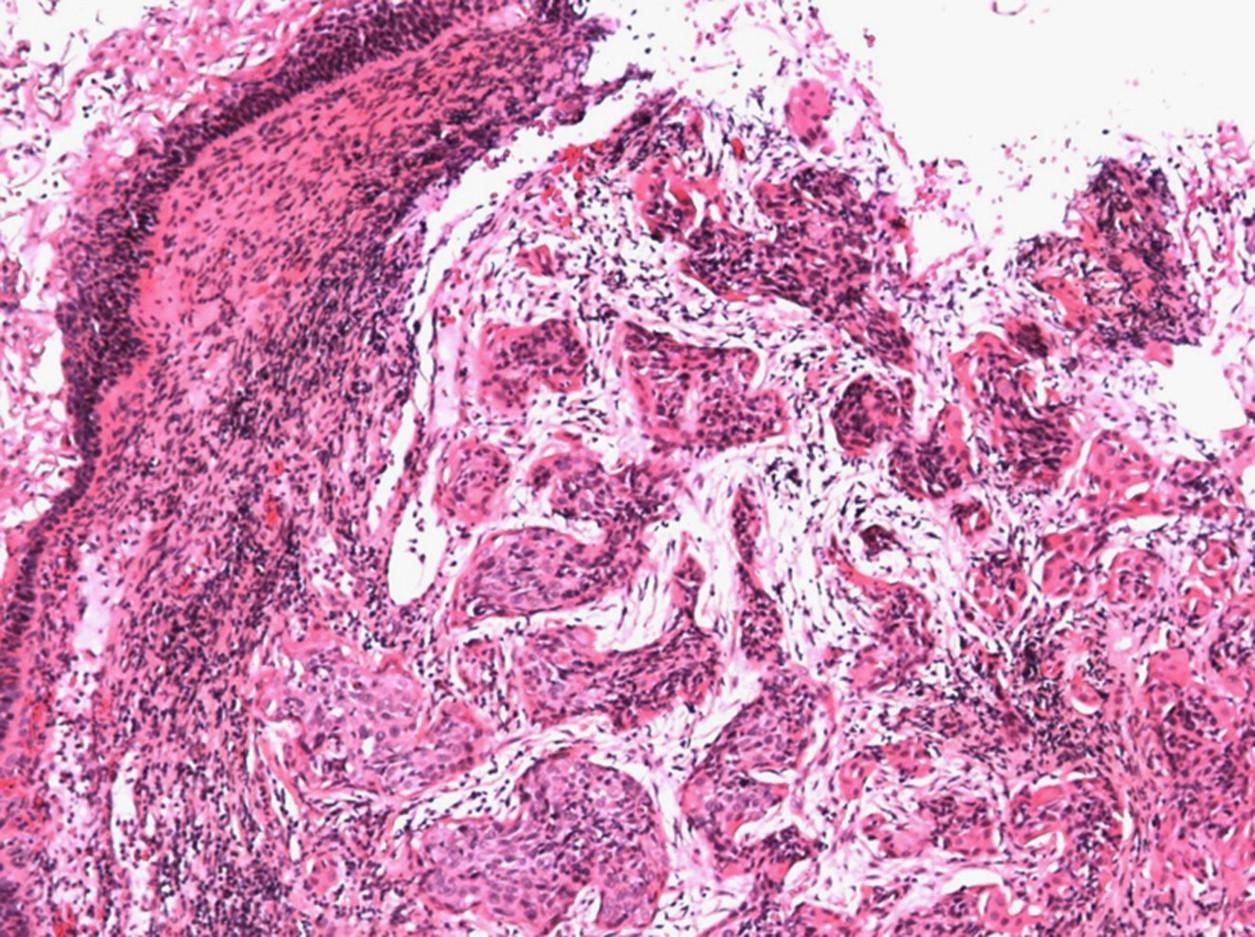

En el laboratorio se observaron muestras patológicas como lo fue una glándula mamaria con cáncer, se fueron realizando hojas de trabajo.También la Dra nos realizó una prueba diagnóstica sorpresa sobre el tema de cáncer Se discutieron casos clínicos sobre el tema de Neoplasias.